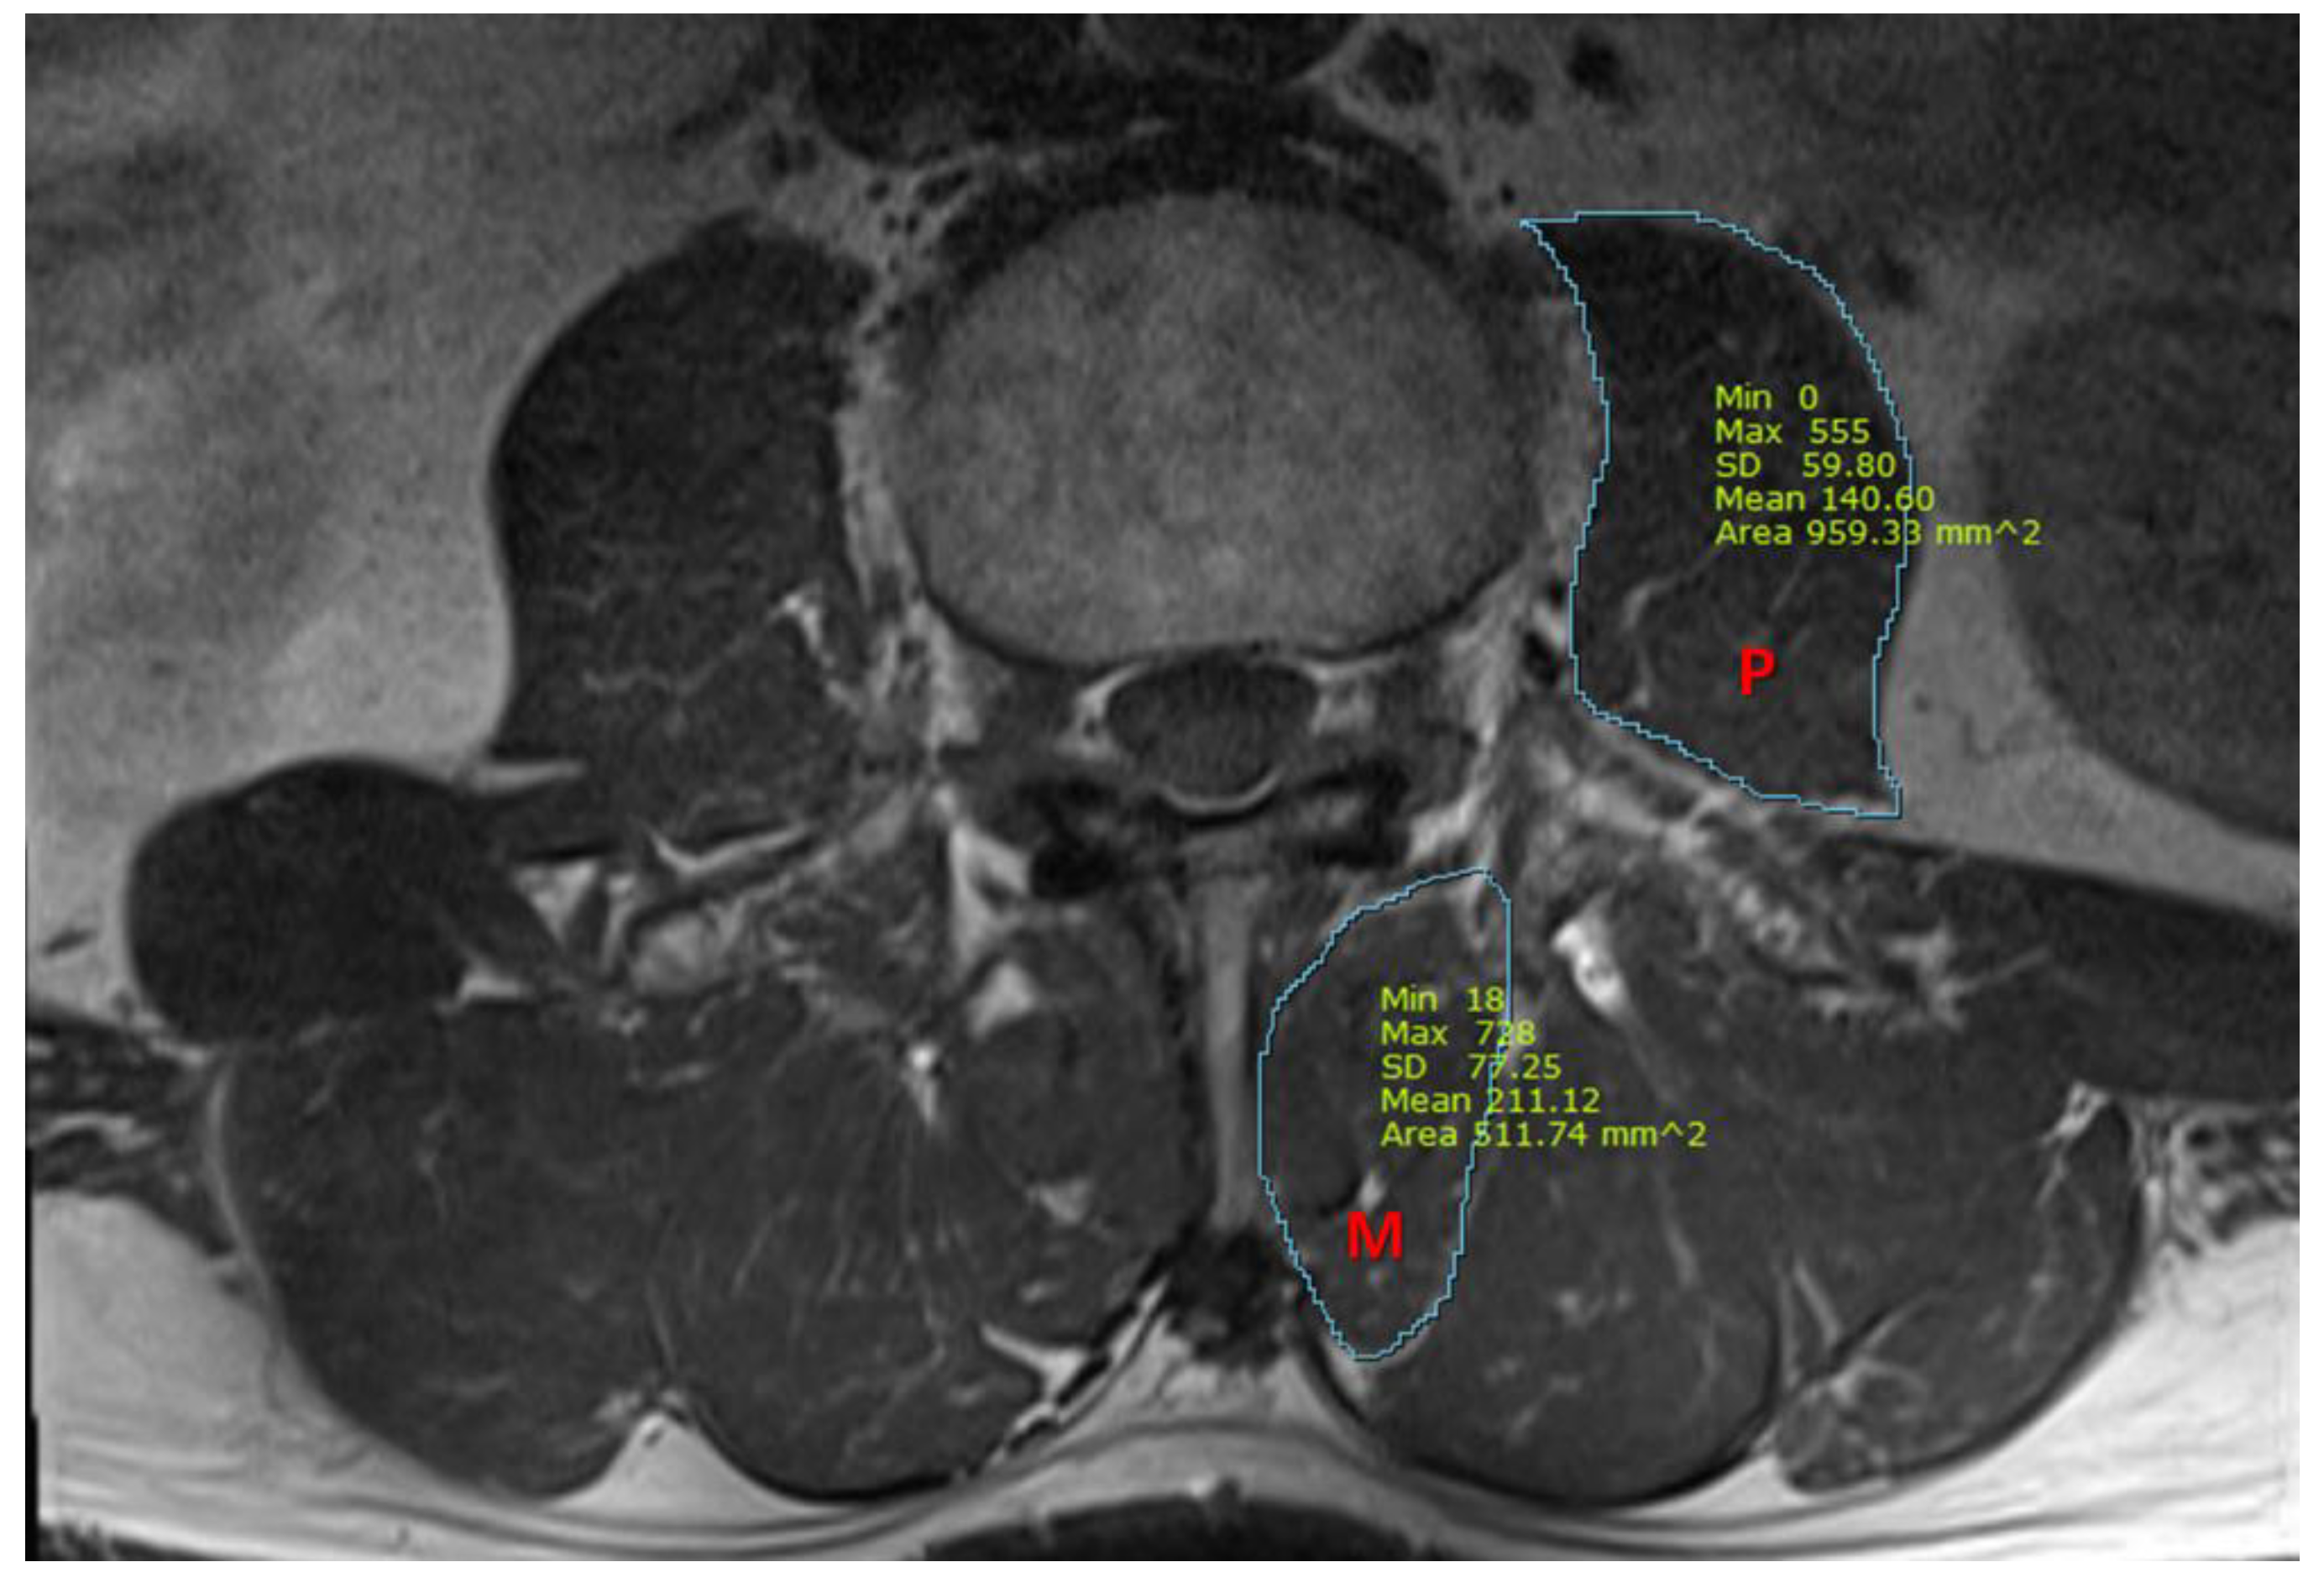

We also measured the cross-sectional area (CSA) of the psoas and multifidus muscles, using T1-weighted axial MRI images at the midpoint of the L3/4 intervertebral disc. Using picture archiving and communication system imaging measurement software (Infinitt healthcare, Seoul, Republic of Korea), the CSA of the multifidus and the psoas muscles were measured, as presented in Figure 1. All measurements were independently analyzed by two pain physicians who were blinded to patients’ characteristics, and a consensus had to be found. In case of disagreement with a difference of more than 15%, images were reviewed together and discussed until the consensus was gained.

Figure 1.

A representative magnetic resonance image for the measurement of cross-sectional area (mm2) of the psoas and multifidus muscles. P, psoas muscle; M, multifidus muscle.